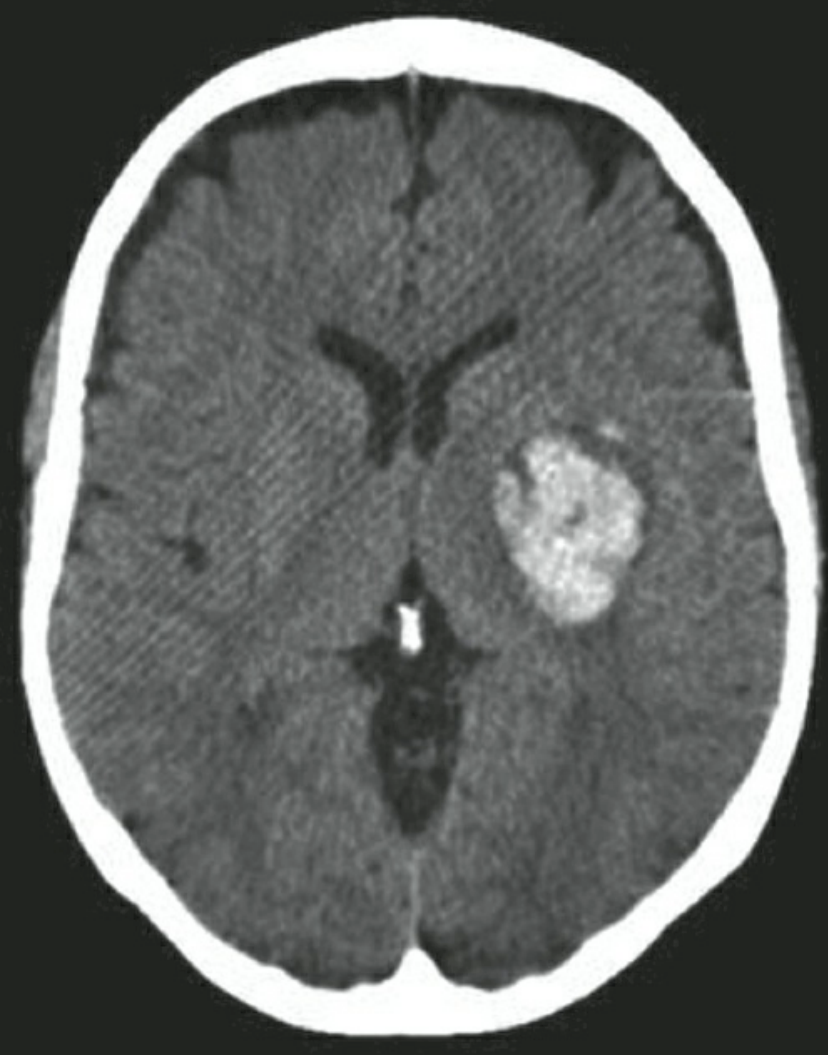

Bệnh nhân nghi ngờ xuất huyết trong não nên được đánh giá và khám thần kinh nhanh chóng. Nên thu thập một bệnh sử ngắn gọn, tập trung vào tiền sử sử dụng thuốc chống đông máu, sử dụng ma túy bất hợp pháp, chấn thương đầu gần đây và tiền sử xuất huyết hoặc đột quỵ não trước đó. CT đầu không thuốc cản quang là công cụ nhanh chóng và sẵn có nhất để thiết lập chẩn đoán ICH. Trong tuần đầu tiên, CT có độ nhạy cao (89%) và độ đặc hiệu (100%) đối với ICH cấp tính. Nó cho phép xác định vị trí giải phẫu của khối máu tụ và khả năng mở rộng vào hệ thống não thất và ước tính thể tích khối máu tụ. Một "dấu hiệu đốm" có thể được quan sát với việc bổ sung thuốc cản quang. Nó thể hiện hoạt động thoát mạch thuốc cản quang vào khối máu tụ và có liên quan đến sự mở rộng khối máu tụ ở 60% bệnh nhân. Chụp CT mạch máu được thực hiện với thuốc cản quang trong giai đoạn cấp tính có độ nhạy tổng thể là 97% và độ đặc hiệu là 98,9% đối với các bất thường mạch máu nguyên nhân, so với chụp mạch máu xóa nền kỹ thuật số (DSA) như một tiêu chuẩn vàng.

Tính thể tích khối máu tụ (mL) = (A x B x C x 0,5 cm) / 2